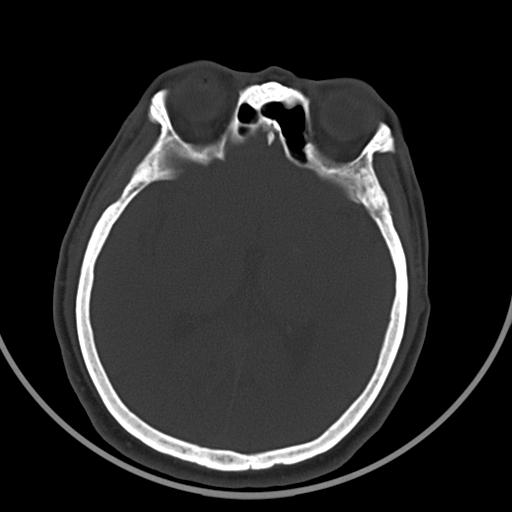

脑梗还是脑穿通畸形

图片尺寸394x395脑动静脉畸形影像学特征 脑动静脉畸形影像学特征

先天性脑裂畸形

图片尺寸600x600